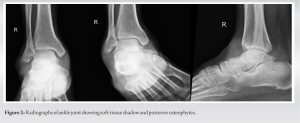

Radiographs revealed diffuse soft-tissue shadow around the ankle with posterior osteophytes in the ankle joint (Fig. 1 and 2).